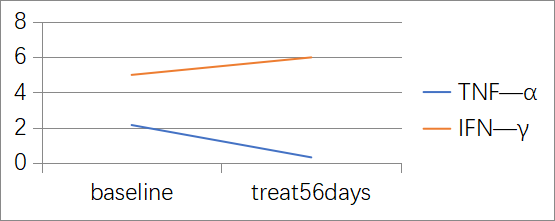

3. IL-6、IL-8和IL-10变化

用药后IL-6和IL-8下降明显,详见图3。

图3. IL-6、IL-8和IL-10水平变化

淫羊藿素软胶囊属于国家中药1.2类新药,是从传统中药淫羊藿中提取、分离、纯化、酶解而来的单体小分子药物。此药的特点是起效缓慢,但是起效后有效时间长,通过下调IL-6、IL-8、TNF-α,上调IFN-γ,改变免疫而达到杀伤肿瘤的作用。2022年CSCO原发性肝癌指南中,淫羊藿素软胶囊用于晚期肝癌一线治疗获得Ⅰ级专家推荐,也是唯一的Child-Pugh评分≤7分或>7分均获推荐的一线方案(IB类证据)。

从作用机制上看,淫羊藿素单体小分子属于免疫调节抗肿瘤药物,可通过直接结合并作用于在免疫系统和癌症发生机理中起重要作用的TLRINF-kB信号传导通道中的靶点蛋白MyD88和IKKα,调控以IL-6/JAK/STAT3为主的炎症和免疫调节信号通路,从而调节肿瘤细胞、肿瘤免疫微环境中不同免疫细胞的多个生物学功能,包括促进肿瘤细胞凋亡,抑制肿瘤细胞生长,抑制炎症因子IL-6、IL-8、IL-10、TNF-α的表达,以及抑制免疫检查点PD-L1的表达。因此,淫羊藿素能够抑制肿瘤细胞生长,同时降低炎症因子和免疫抑制来促进免疫功能的恢复,改善肿瘤炎症免疫微环境。